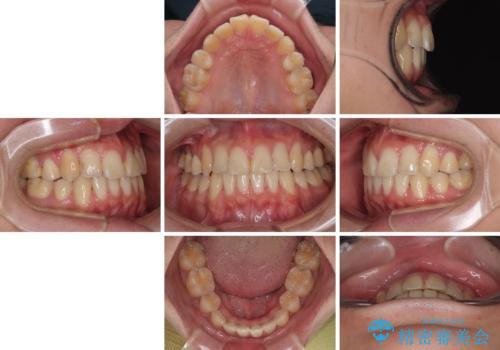

- 高校生の時に行った抜歯矯正の後戻りを気にして来院された患者様です。

インビザラインでの治療を希望されていて、デコボコの程度が中等度であり、安価なパッケージにて対応可能と判断されたため、インビザライン・モデレートを用いて矯正治療を行うこととしました。

- インビザライン・モデレート

- 10ヶ月

- 2-5回

インビザライン・モデレートは、製作できるアライナーの枚数に制限があるため、移動可能な量に限りがあるものの、インビザライン・ライトよりも枚数が多いため、幅広い症例に対応可能です。